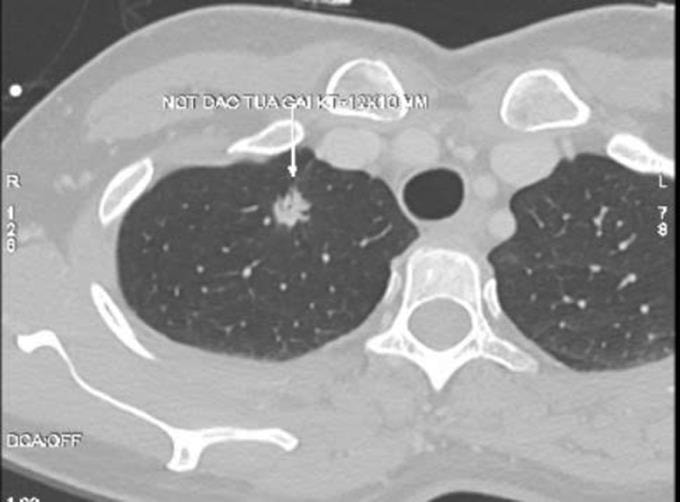

Kết quả chụp CT tại Bệnh viện Đa khoa Tâm Anh Hà Nội cho thấy phổi phải của bà Liên có nốt đặc tua gai, kích thước khoảng 12x10 mm, xếp loại Lung-RADS 4X. TS.BS Vũ Hữu Khiêm, Trưởng khoa Ung bướu, giải thích 4X là phân loại cao nhất trong hệ thống Lung-RADS, cho thấy tổn thương có đặc điểm hình ảnh bất thường, nguy cơ ác tính cao.

Nốt phổi nguy cơ cao của bà Liên trên phim chụp CT. Ảnh: Bệnh viện Đa khoa Tâm Anh